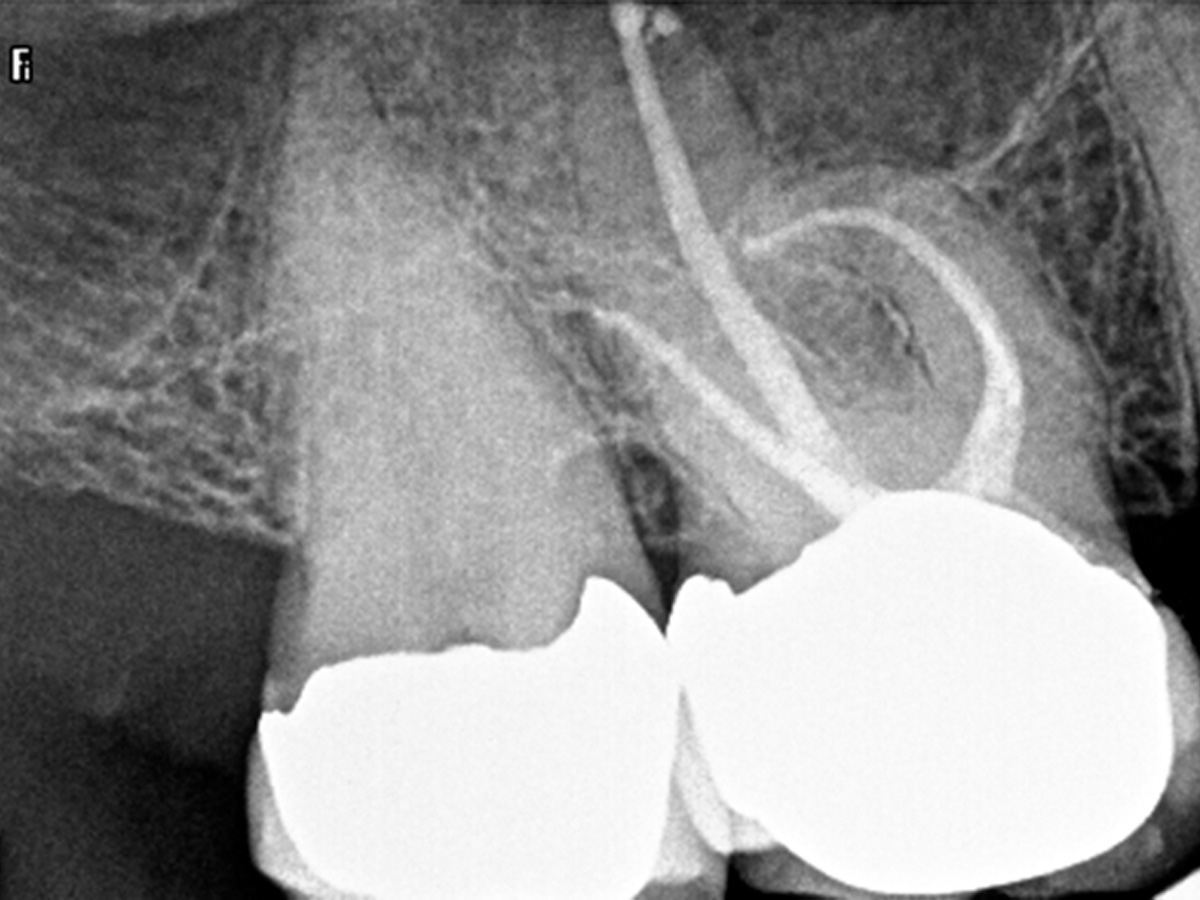

Abbildung 4

Die klassische Aufbereitung bei gekrümmten Kanälen erfolgt durch Erweiterung des Kanaleingangs mit konventionellen Stahlbohrern (Gates Glidden) oder NiTi Introfeilen mit höherer Konizität, was zu einer unnötigen Entfernung von Dentin am Kanaleingang führt (oranger Bereich). Um diese zu vermeiden wurden die Kanäle mit wärmebehandelten Niti-Feilen der neuesten Generation (FKG RACE EVO) bei 1.000 rmp/ 1,5 N-cm aufbereitet.

Abbildung 5

Der maschinelle Gleitpfad wurde mit der RACE EVO 15.04 geschaffen und die Kanäle bukkal bis 35.04 und palatinal bis 50.04 präpariert.